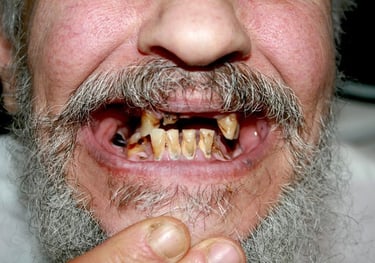

Children's dental health in El Salvador faces significant challenges, with high rates of untreated early childhood caries (tooth decay) linked to chronic exposure to sugary drinks and snacks, which are often cheaper than safe drinking water. Lack of education about proper oral hygiene, limited access to dental care, and socio-economic factors contribute to a cycle of decay, pain, and malnutrition. Community-based interventions including education, and distribution of oral care products show promise but face limitations and challenges.

The dental situation for adults in El Salvador is challenging, characterized by widespread tooth loss (edentulism) and periodontal disease. Poor oral hygiene is a contributing factor, linked to factors such as diets high in sugar and lack of access to proper dental education.